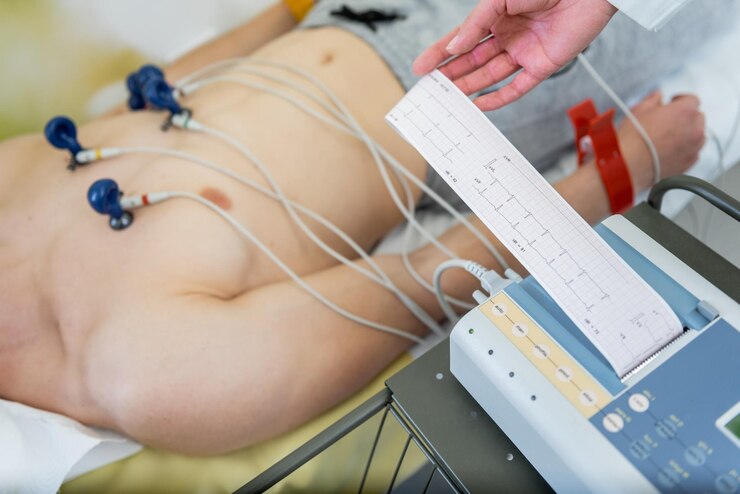

Dr. Jagannatha Raju is the best cardiologist in Vizag, offering expert heart care at Varma Hospitals.

With 20+ years of experience, he specializes in advanced diagnosis and treatment of heart conditions.

His dedication to patient well-being ensures high-quality and compassionate healthcare.

Trust Dr. Jagannatha Raju for the best cardiac care in Vizag.